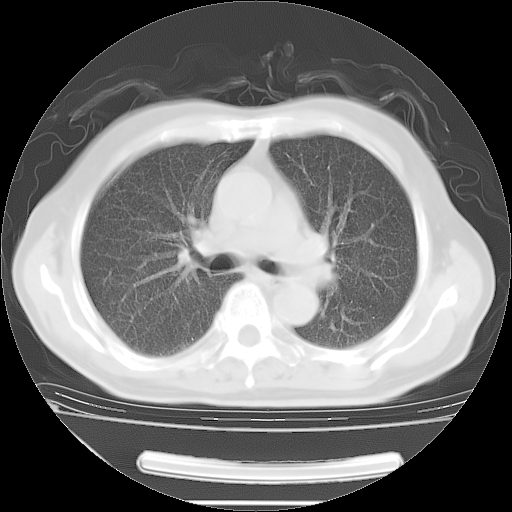

今天复查肺部CT,发现双肺广泛磨玻璃样改变。所以我把3月19日和5月9日相隔50天的肺部CT上传。请大家会诊。

5月9日肺部CT(在4月27日齐鲁医院肺部CT描述部分肺组织磨玻璃样改变,12天后肺组织广泛磨玻璃样改变)

大致读了系列胸部CT:纵隔窗无明显异常,肺窗:从4、27至今:主要是双肺中下野外带可见毛玻璃样改变,目前处于急性肺泡炎阶段,至于原因考虑1、结替组织或胶原血管性疾病所致?2、恶性疾病如恶组在肺部所致的表现或细支气管肺泡癌?3、药物或其它原因如肺蛋白沉着症所致肺泡炎目前不太可能?总之,明天就去请我院的呼吸科、感染科、血液科和临免专家会诊哈。